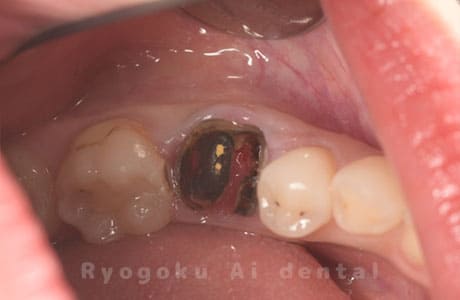

Case27

-

重度カリエス

歯牙移植咬合面術前 -

移植する親知らず

歯牙移植術直後咬合面

歯牙移植術後咬合面

歯牙移植術前側面

歯牙移植術中側面

歯牙移植術後側面

- 原因

- 重度カリエス

- 治療内容

- 自家歯牙移植、部分矯正

- 治療費用

- 220,000円(移植費用)

110,000円(部分矯正費用)

虫歯が大きく、保存不可能となった歯を上の親知らずと交換する自家歯牙移植を行いました。移植歯が小ぶりであったため、部分矯正を行い問題なく噛み合い、経過良好です。